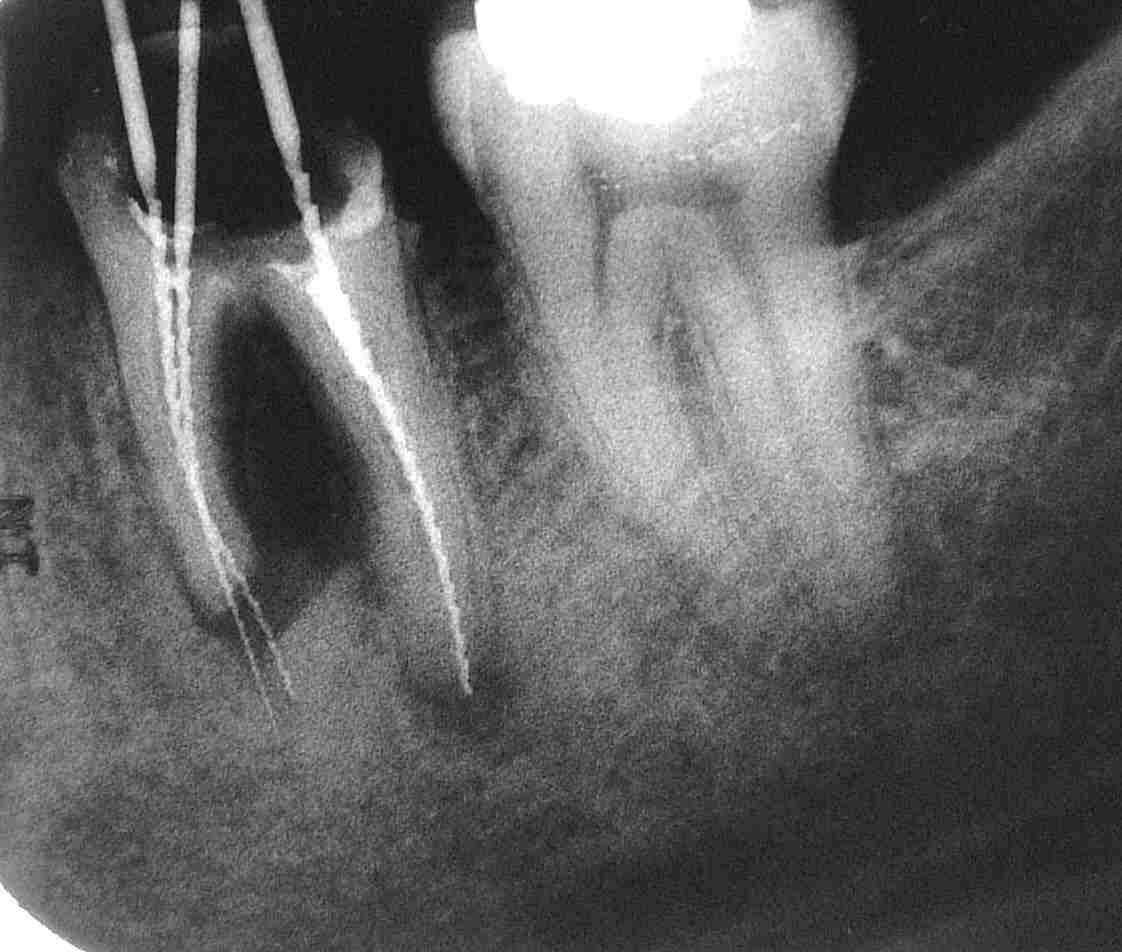

………………hätten sie bei diesem Zahn 36 einen Erhaltungsversuch für erfolgversprechend gehalten? Nicht wirklich? Dann befinden Sie sich in guter Gesellschaft mit unserem vorletzten Ausbildungsassistenten. Auf unseren eindringlichen Rat („Extrahieren können Sie immer noch!“)  hin hat er es dennoch versucht: